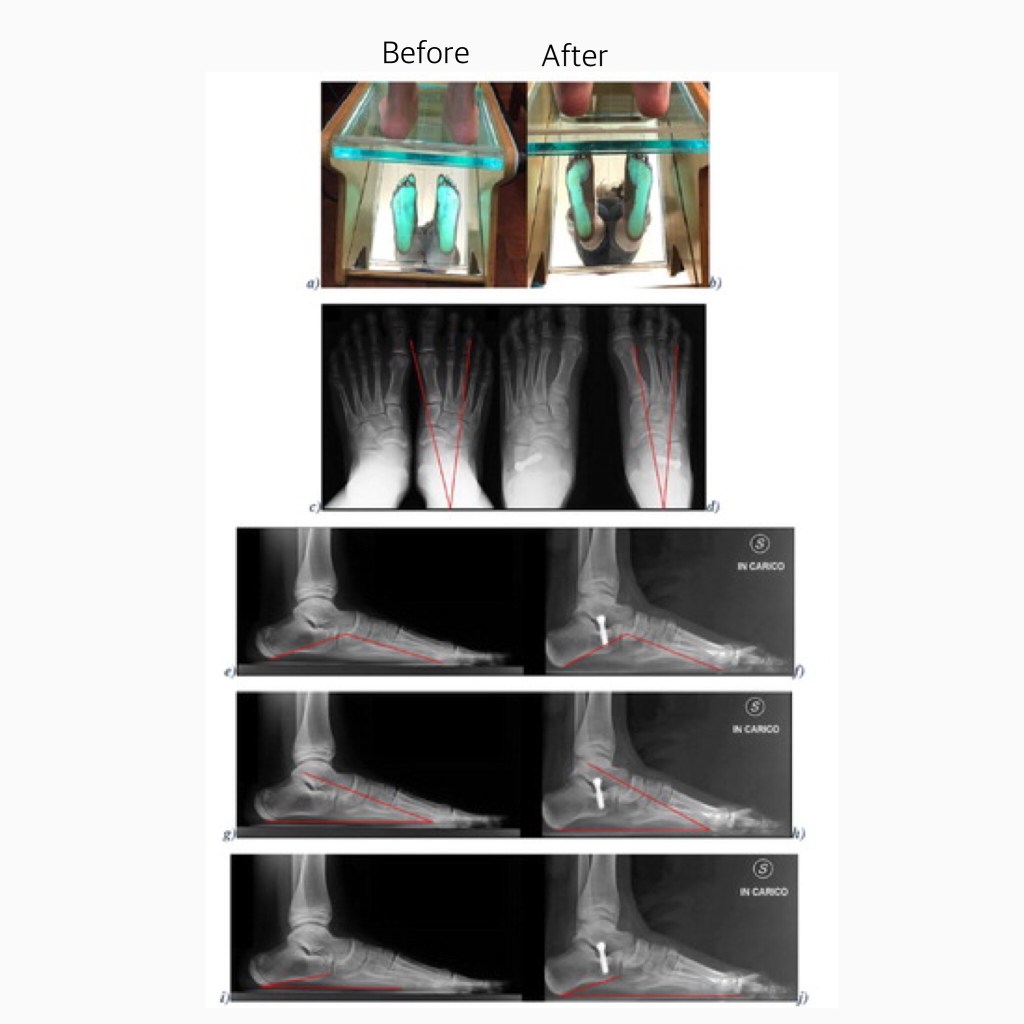

El tope de calcáneo es una técnica barata, sencilla y eficaz para corregir los pies planos flexibles infantiles sintomáticos que no han respondido a las medidas conservadoras. La técnica corrige el pie a corto plazo y esta corrección se mantiene en el tiempo.

Los tornillos están recubiertos de platino y se colocan entre dos huesos ayudando a desplazar el hueso que sujeta el arco del pie plano. Los tornillos se mantienen alrededor de dos años dentro del cuerpo, al caminar los tornillos desvían los huesos formando el arco del pie.

A veces el arco del pie es demasiado plano y el cirujano puede decidir poner un tornillo más o cambiarlo por uno más largo dos años después.